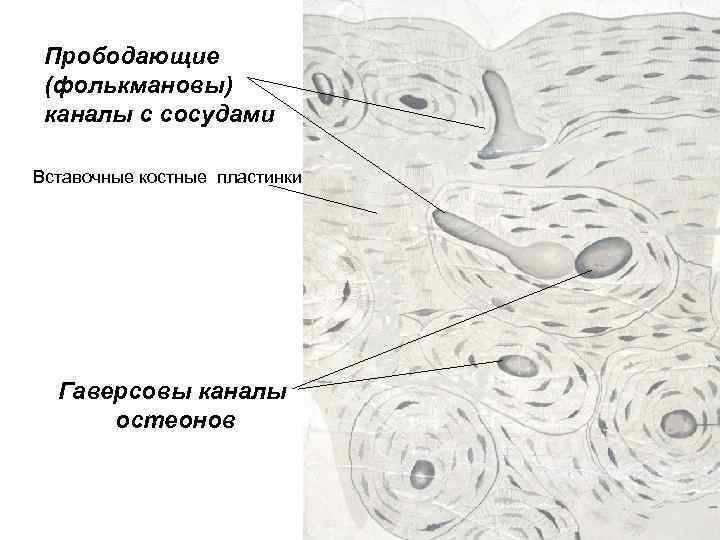

Структура грубоволокнистой костной ткани: наглядные примеры